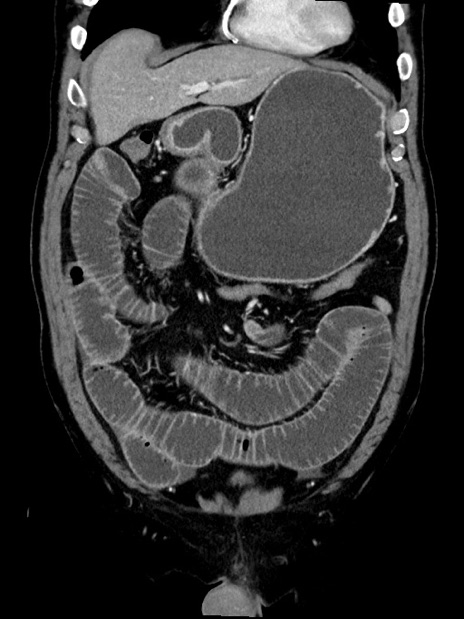

症例35(冠状断像)

【症例】70歳代 男性

【主訴】腹部膨満、嘔吐

【現病歴】昨日より腹部膨満感出現。本日増悪し、仙痛出現。嘔吐あり、受診。

【既往歴】糖尿病、胆摘後

【身体所見】BP 149/80mmHg、HR 74/min、BT 35.9℃、腹部:膨満、軟、圧痛なし。腸雑音減弱あり。上腹部正中切開瘢痕あり。

【データ】WBC 13500、CRP 1.72